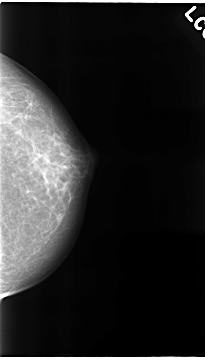

C_0069_1.LEFT_CC

LEFT_CC LINES 4672 PIXELS_PER_LINE 2664 BITS_PER_PIXEL 12 RESOLUTION 50 NON_OVERLAY